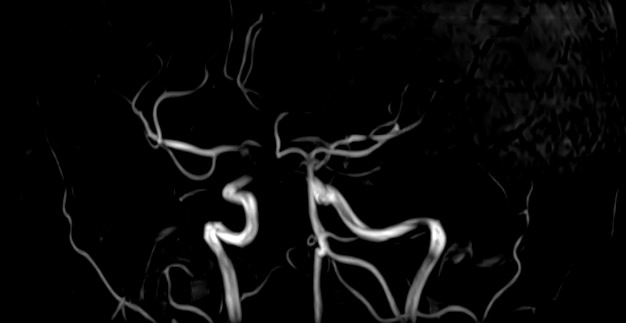

Магнитно-резонансная ангиография артериальной и венозной систем головного мозга позволяет получить трехмерное изображение сосудистой системы, кровоснабжающей центральную нервную систему, оценить анатомическое строение артерий и вен головного мозга и функциональные особенности кровотока.

С помощью внешнего магнитного поля томограф послойно сканирует структуры головного мозга, затем посредством компьютерных программ преобразует полученные данные в трехмерное изображение. При этом на снимке видна только сосудистая система без окружающих тканей. Таким образом, сканирование в режиме ангиографии позволяет визуализировать артерии и вены головного мозга без контрастирования.